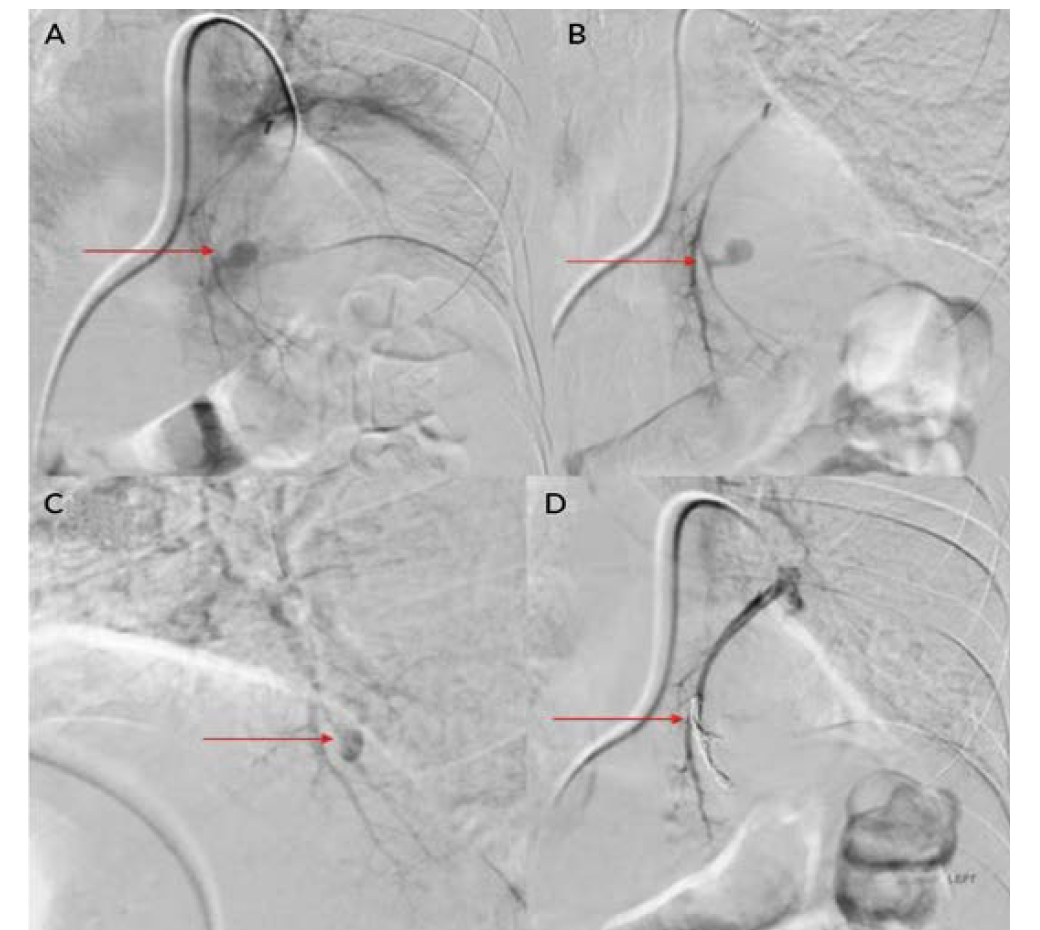

Eight patients were included during this study period; all were men between ages 34 and 61 (Table 1). Positivity to COVID-19 RTPCR test was detected over a period of 2 to 6 months prior to the acute hemorrhage. Six patients presented with massive hemoptysis; 2 presented with severe epistaxis. A contrast-enhanced computed tomography angiography was done in all patients. All 6 patients who presented with massive hemoptysis were detected to have pulmonary arterial pseudoaneurysms with associated cavitary lesions in the lungs (Figure 2). Among the 2 patients who presented with nasal bleed, 1 had a biopsy and culture-proven invasive fungal sinusitis with an internal maxillary artery pseudoaneurysm, probably of mycotic etiology. The second patient also diagnosed with invasive fungal sinusitis had multiple sinonasal debridements outside before presenting with massive epistaxis wherein a diagnosis of internal carotid artery pseudoaneurysm was made, probably secondary to iatrogenic or mycotic etiology. The presence of concomitant COVID-19 infection in these patients predisposed them to impairment of cell-mediated immunity, immune dysregulation, and a decrease in CD4 and CD8 counts, increasing their vulnerability to fungal infections. In 6 patients it was possible to obtain samples for fungal elements through biopsy. Endovascular embolization was performed under local anesthesia in 7 patients, and under general anesthesia in 1 patient. Different embolic agents were used: coils (Figures 3A and 3B), Amplatzer vascular plug (Abbott) (Figures 4A and 4B, Figures 5A and 5B), and glue (Figures 6A and 6B). However, 2 patients underwent lobectomy for extensive parenchymal disease apart from pseudoaneurysm. One patient with pulmonary artery pseudoaneurysm had contrast extravasation into the cavity during the procedure. All patients had cessation of hemorrhage. However, 2 patients required pulmonary lobectomy because of extensive parenchymal disease after embolization for the pseudoaneurysm.

Endovascular intervention is a minimally invasive technique that is used to treat these types of pseudoaneurysms.4-6,11 Pulmonary artery pseudoaneurysms can be treated with multiple techniques, such as coil embolization of the involved artery, plug placement within the involved artery, glue embolization of the aneurysm, and placement of a stent graft across the aneurysm.4,10,11 If the aneurysm is peripherally placed and is not accessible via a transarterial approach, ultrasound-guided injections such as thrombin or glue can be tried.14 The endovascular approach is minimally invasive compared with surgery.9,10 Mortality, morbidity, and complication rates following endovascular intervention are lower compared with surgery.5,11 Hospital stays following endovascular intervention are usually lower.9,10 Endovascular embolization has an initial success rate of 95%, and surgery is reserved for those patients where multiple sittings of embolization have failed.4,5,10